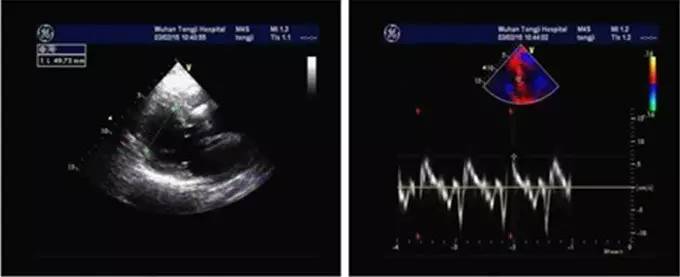

患者入院后完善超声心动图检查(图2),结果显示心脏形态正常,结构无明显变化,仅存在左室节段性室壁运动异常[二尖瓣口左房侧以及三尖瓣口右房侧收缩期可见轻度反流血流信号及湍流频谱;二尖瓣口舒张期血流频谱测值:E峰96 cm/s,A峰58 cm/s;左室射血分数(LVEF)66%;室间隔二尖瓣环处E' 10 cm/s,A' 10 cm/s,S 7 cm/s]。但值得关注的是,虽然看似心功能尚可,但与患者症状不符,而其关键点就在于该患者存在射血分数保留的心力衰竭(HFpEF)。

图2. 超声心动图检查